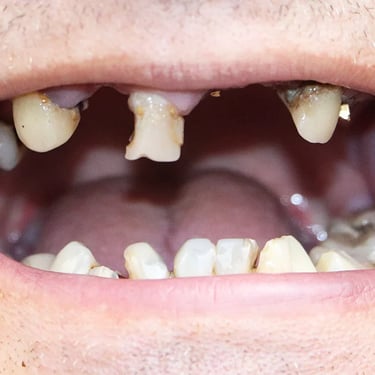

Edentulismo completo

El edentulismo completo es la ausencia total de dientes en una o ambas arcadas.

Los pacientes tienen dificultad para masticar, hablar y pueden sentirse incómodos con su apariencia.

El tratamiento puede incluir la colocación de una prótesis completa sobre implantes, proporcionando una solución fija y estable